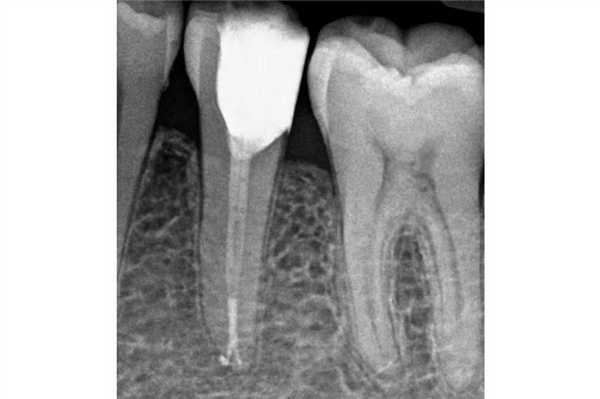

Непрямые реставрации с адгезивным механизмом фиксации являются довольно частым выбором врачей-стоматологов, учитывая их эстетичность и консервативность. Данный тип реставраций также способствует сохранению большего объема тканей зуба. Однако при фиксации подобных конструкций необходимо контролировать уровень влажности рабочего поля, дабы не компрометировать силу бондинговой связи. Удаление излишков композитного цемента часто может вызвать кровотечение с поддесневой области, и таким образом нарушить весь адгезивный протокол. В долгосрочной перспективе такие последствия ассоциированы с эффектом микроподтекания и расцементировки коронки. DME может помочь решить подобные проблемы и оптимизирует условия для фиксации коффердама (фото 1).

Дефект поддесневой локализации гораздо проще восстановить прямой реставрацией. Во-первых, требуется меньше времени, следовательно, контроль над влажностью может быть менее продолжительным. Кроме того, врачу доступны разные системы матриц, которые способствуют восстановлению поддесневого дефекта. Но при этом DME следует использовать лишь в том случае, если можно обеспечить надежное уплотнение композитного материала.

Какие материала использовать для прямой реставрации?

Техника DMЕ изначально была разработана для восстановления глубокого края дефекта зуба посредством композитного материала. Ведь при фиксации непрямой окончательной реставрации за счет адгезивной связи таковая может «приклеится» непосредственно к поднятому из глубины композитному краю. Концепция DME также может быть реализована и за счет амальгамы или стеклоиономерного цемента. Для оценки адаптации реставраций необходимо использовать рентгенографию «в прикус» (bite-wing): это позволяет идентифицировать нависающие края или «недолеты» композитного восстановления.

DME является полезным клиническим подходом, который эффективно работает в конкретных клинических случаях. Современные данные указывают на то, что непрямые реставрации зубов, предварительно прошедших процедуру DME, демонстрируют успешный результат функционирования на протяжении длительного времени. Во многих случаях DME остается последним шансом восстановления проблемных зубов с глубокими дефектами. Перед началом лечения пациент должен быть проинформирован о всех преимуществах и недостатках подобного алгоритма вмешательства, а также относительно потребности в проведении тщательной очистки проблемных участков с помощью межзубных ершиков, которые обеспечивают поддержку здорового состояния тканей пародонта.